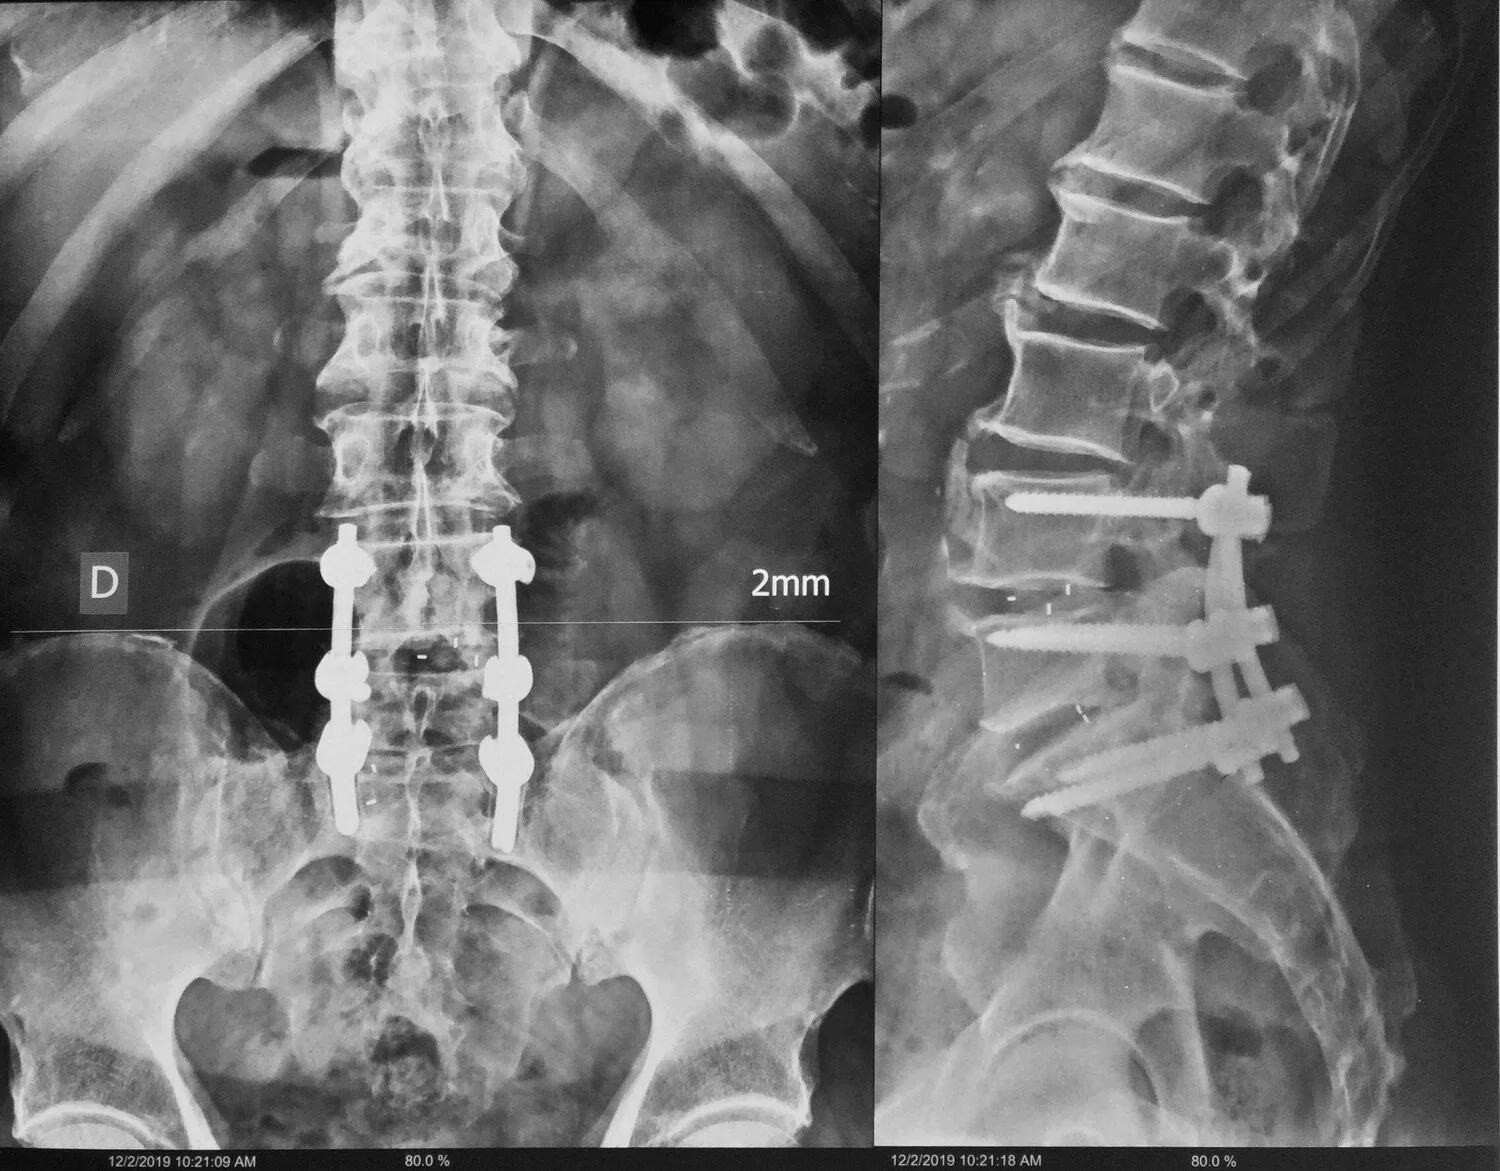

Cirugía de columna vertebral

Unión craneovertebral; Mielopatía Espondilótica Cervical; Estenosis raquídea; Hernias de disco; Instrumentación Occipitoatlantoaxial; Tumores óseos; Tumores de médula espinal; Tumores de nervios y raíces nerviosas; Siringomielia; Escoliosis; Cirugía para corrección del balance sagital.